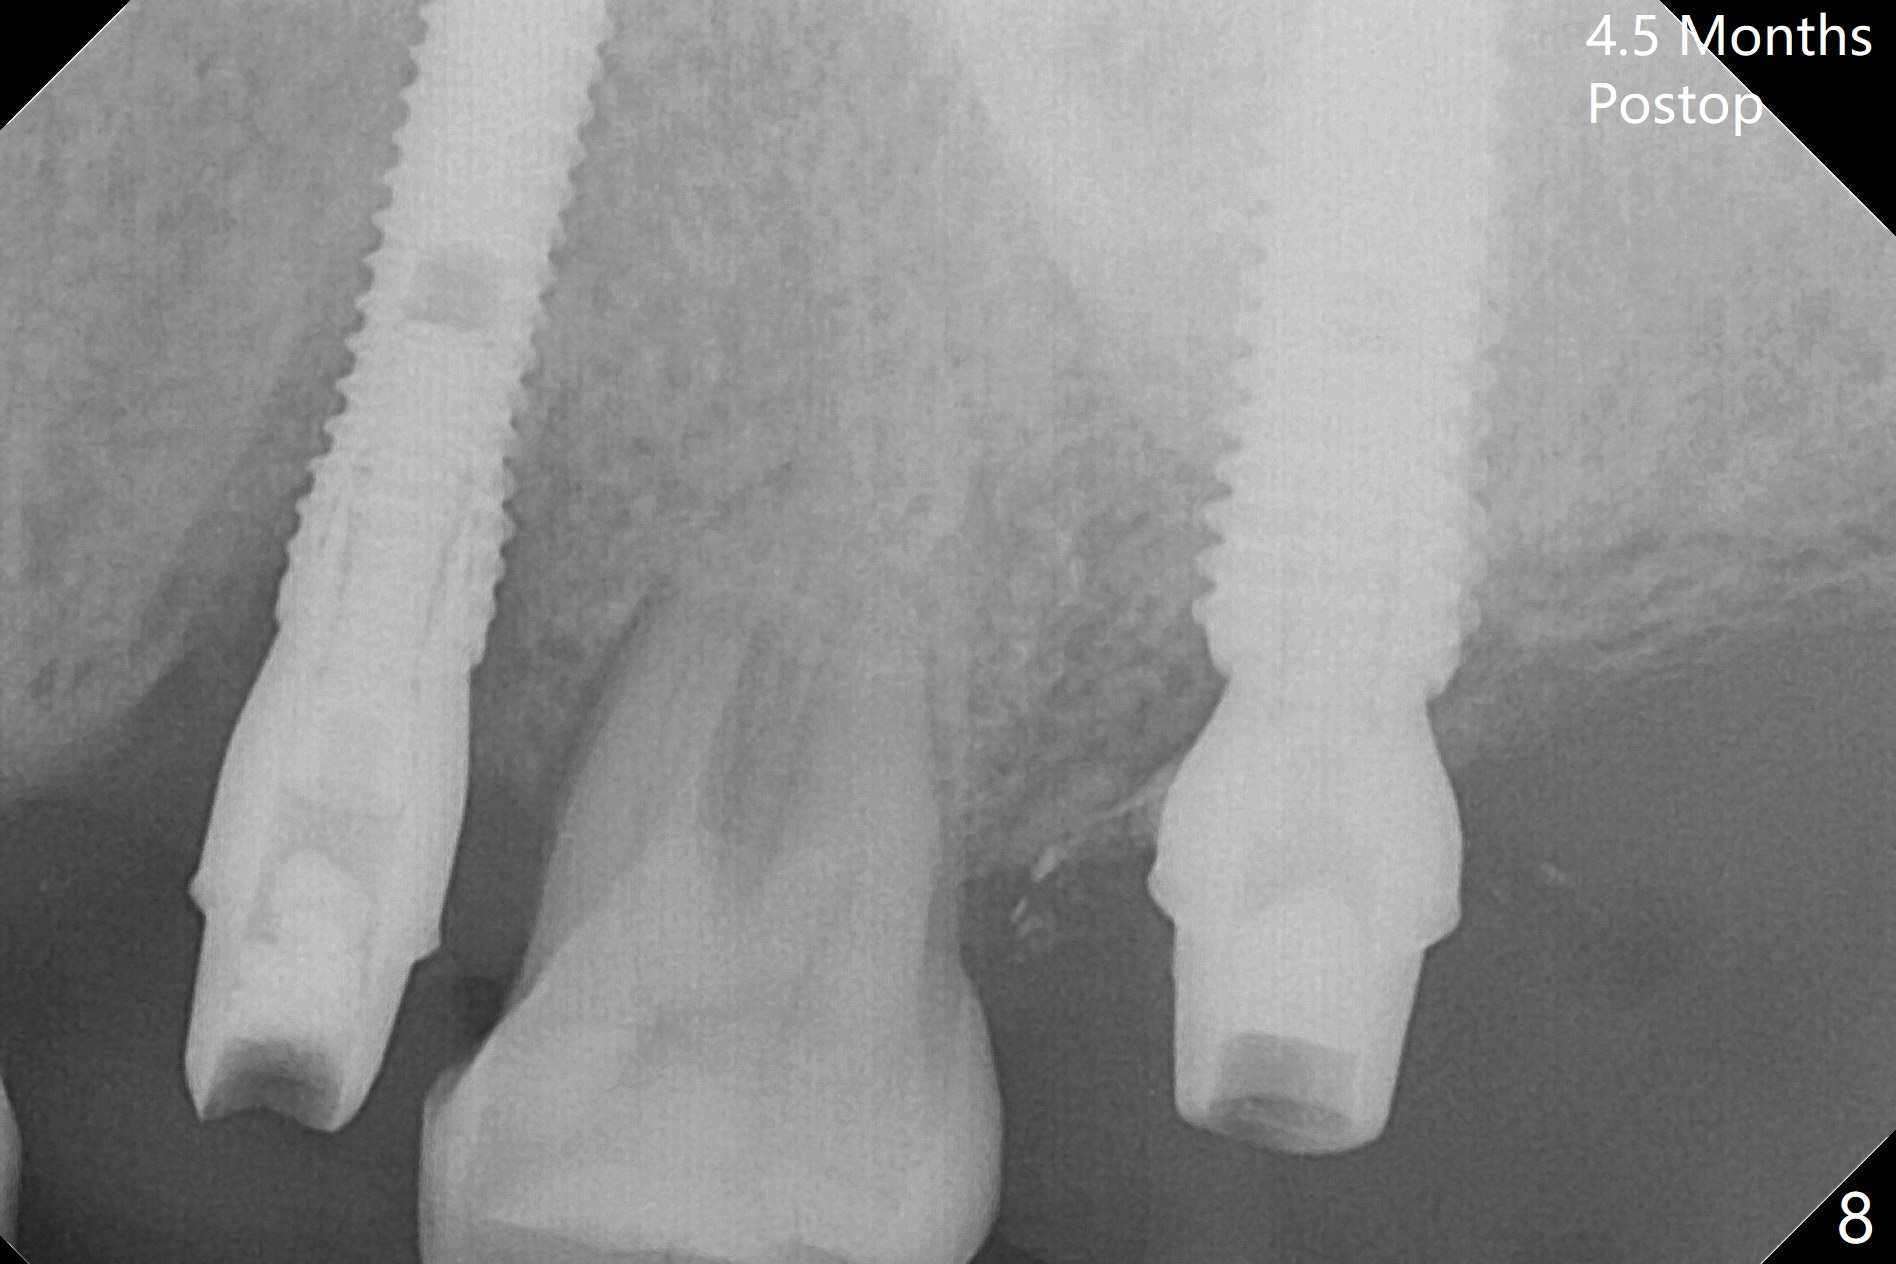

A 1.2 mm initial drill is used to start osteotomy at the site of #15 (Fig.1). After moving the osteotomy distally (with Lindamann bur), the osteotomy is enlarged by DIO Bone Expanders until 2.4/3.7 mm for 18 mm (gingival level) (Fig.2). Following the expander 3.0/4.4 mm, a 5x13 mm UF implant is placed supracrestal (Fig.3,4). After deepening the osteotomy with 3.8 mm drill for 3 mm, the implant is placed deeper by ~ 2 mm (Fig.5 arrow). Since the tooth #18 is supraerupted, a healing abutment (5.5x12(3) mm) is placed (Fig.6: H); the gingiva adapts to the abutment well. Suture is not necessary. The bone remains stable 2 and 4.5 months postop (Fig.7,8). Impression is taken. A crown is delivered nearly 6 months postop (08/07/2017). While there is minimal bone loss at #13 and 15 three years and 4 months post cementation, the tooth #14 and 18 are mobile (Fig.13,14, #13).